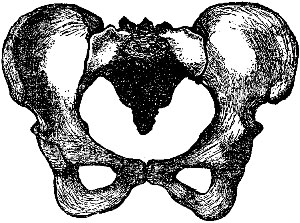

The Pelvis.—The pelvis is the bony framework which forms the lower part of the body. On each side it forms a union with the hip bone to make the hip joint.

The female pelvis contains the reproductive organs (uterus, vagina, and ovaries), and also the bladder and lower bowel.

Fig. 2 gives a very good idea of the shape and general structure of this bony framework; while a careful study of Fig. 3 will enable one to form a very correct idea of the relative size and position of the various parts contained in this framework.